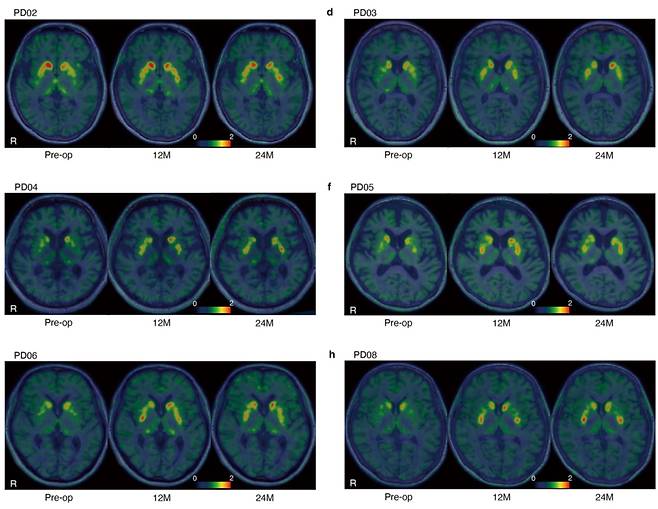

일본 교토대 연구진은 파킨슨병 환자를 대상으로 진행한 임상 1·2상 시험 결과를 담은 논문을 17일 국제 학술지 네이처에 게재했다. 임상시험은 교토대병원에서 50~69세 환자 7명을 대상으로 진행됐다. iPS세포를 도파민 신경세포로 자랄 전구세포로 분화시킨 다음, 환자 7명(저용량 3명·고용량 4명)의 뇌에 이식하고 24개월간 추적 관찰했다.

시험 결과, 안전성에 문제가 없는 것으로 나타났다. 연구진은 “이식한 세포가 과도하게 자라 종양이 되는 수준의 중대한 부작용은 나타나지 않았다”고 밝혔다. 경증·중등도 수준의 이상반응은 73건으로 보고됐다. 자기공명영상(MRI)에서도 이식 세포의 과성장이 관찰되지 않았다. 일부 환자에서 떨림이나 강직 증상이 줄어드는 치료 효과도 확인했다.

교토대 연구진은 “동종 iPSC 유래 도파민 전구세포가 투여 후에도 생존하고 도파민을 생성하는 한편, 종양을 형성하지 않는다는 점을 입증한 것“이라며 ”파킨슨병에 대한 안전성과 잠재적 임상 유효성(치료 효과)을 시사한다”고 밝혔다.